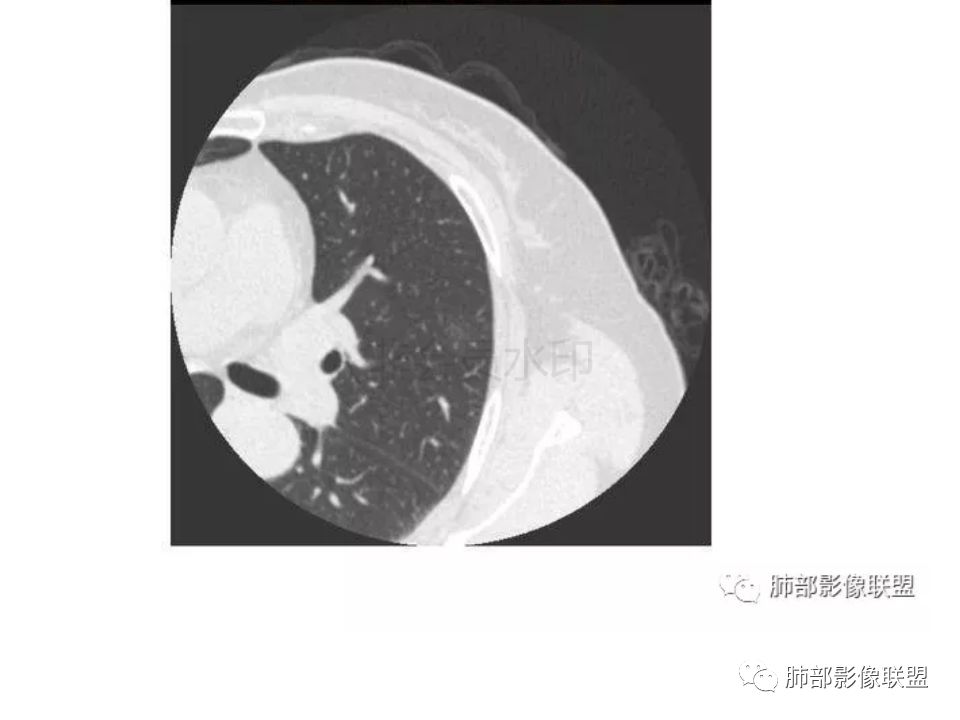

【每日晨读】腺癌VS隐球菌

三生石上:支气管有截断,周围有晕,有空泡,腺癌?毛勤香:左肺下叶近胸膜下结节,周围磨玻璃影,边界似稍模糊,局部细支气管截断,实性区和磨玻璃区分界突然,隐约细毛刺,首先考虑感染性,隐球菌?待排腺癌MIA伴肺泡塌陷可能。常规治疗后复查。Coke with ice:IACM-Imaging :孤立胸膜下结节,其内见小泡,周围模糊的晕,晕中软毛刺,近端与血管相连,血管自然通过,气管进入结节内部一半,猜个隐球吧。第二腺癌,建议复查。田园晚风:考虑腺癌紫气东来:左肺上叶,磨玻璃实性毛刺,空泡,支气管截断,腺癌雪颜:左肺上叶结节状密度增高影,周围有晕,感觉周围模糊,有血管进入,里面有空泡征,隐约看到里面有支气管穿过,考虑炎性,隐球菌感染?腺癌待排THINKER:上叶尖后,SPN,有晕,软毛刺,无胸膜凹陷,分叶丶收缩不明显,支气管进入,远端阻塞,首选肉芽肿,PC或炎性结节,有一支血管滋养,鉴别腺癌,增殖性结核结节不支持期:左上肺结节周围有晕 晕中见细软毛刺 首先考虑隐球菌一米阳光:左肺上叶磨玻璃影,空泡,周围毛刺,月牙铲,支气管通过,周围有晕,考虑腺癌我的FY:毛刺,小空泡,磨玻璃考虑恶性崔少钢:小病灶,内有支气管,空泡征,实变不规则,放大了,感觉晕有点偏清,考虑恶性。小病灶里面有支气管是值得高度怀疑的。没有病史。彭君:左肺上叶舌段结节 周围晕模糊 内小支气管扩张 近端与血管相连 自然通过 首先考虑炎性 隐球菌?边缘月牙铲 腺癌待鉴别徐婕:左上肺结节周围有晕 ,晕中见细软毛刺 ,晕边界不太清,先考虑隐球菌张帅:左肺上叶尖后段实性病灶,以细支气管为中心,周围呈毛玻璃样影,并可见密集分布毛刺,内可见支气管征,支气管呈壁呈结节样改变,病灶周围可见血管增粗。考虑 淋巴瘤?鉴别隐球。张延军:混合型磨玻璃结节,伴毛刺,支气管截断,空泡,考虑浸润性腺癌,建议抗炎治疗后复查XGQ:支持隐球春秋:结节伴晕征,晕中毛刺,相邻小支气管近端进入,远端阻塞,近端血管相连,首先考虑隐球菌王秀仙:左肺上叶混合型磨玻璃结节,支气管截断,空泡,有毛刺,考虑浸润性腺癌,建议抗炎治疗后复查玫:左肺上叶磨玻璃结节影,薄扫见长短不一毛刺,有空泡,病灶边缘见晕征,考虑小腺癌可能,不除外炎性结节。zyf:左肺下叶近胸膜下结节,周围有晕,细软毛刺,有支气管进入,实性区和磨玻璃区分界明显,首先考虑感染性,隐球菌?查隐球菌荚膜抗原!RockJ-ason:考虑隐球采莲:左上肺靠近胸膜下实性结节影,边缘模糊,周围有晕及晕中毛刺,支气管进入通畅,有小空泡。考虑炎性病变,隐球可能性大。鉴别结核。Harvey:左肺下叶舌部小结节,边缘见磨玻璃影,边界欠清,内见支气管、管壁不光整,偏向恶性。鉴别隐球菌lmg:左肺上叶混合小结节,有晕,边界模糊,有有小毛刺。考虑炎性病变,隐球收选。AIS并肺泡塌陷带排。山河:倾向腺癌红日东升:GGO边界似清非清,内部好像不是小空泡,是小支气管腔,倾向炎性病变,常规抗炎复查除外腺癌,尤其粘液腺癌。

我怎么感觉支气管是通的,周围的晕又比较软,我考虑炎性病变,隐球菌可能大(如下图)

隐球菌感染孤立病灶与肺腺癌结节在影像上有时难分彼此,尽管隐球菌胸膜下更常见。

1.隐球菌病灶往往是实性密度结节为主伴周边边界不清楚的晕,有时可见晕内细软毛刺。

微浸润腺癌常常是磨玻璃密度为主的结节,边界比较清楚,并似乎有弧线形小叶间隔阻挡的痕迹。

实性结节的腺癌则很少有磨玻璃晕,往往会有粗短的硬毛刺。

2.隐球菌病灶形态往往圆钝柔和,缺乏收缩能力,很少出现腺癌的那种胸膜牵拉和棘状突起。

3.病灶内支气管安然无恙隐球菌病灶更加多见

4.隐球菌病灶增强扫描可轻度强化。既不同于结核灶的几乎不强化,也不同于肺腺癌的明显强化。

该患者实性成分为主,可惜未提供增强扫描图像。